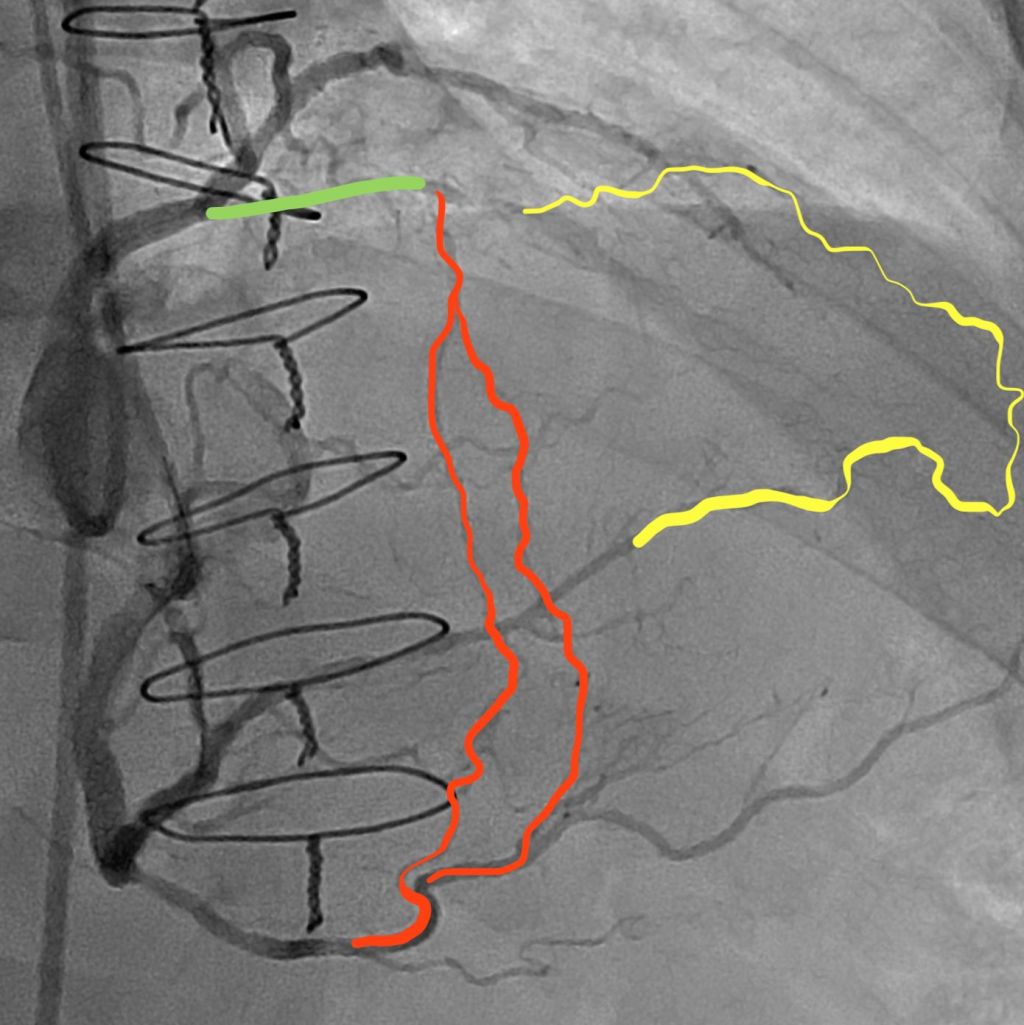

87 year old extremely pleasant, active woman was sent to us for complex LM PCI . She has distal left main 70% disease, ostial LAD 70% disease, calcific 90% disease of the proximal high Obtuse marginal artery and 99% Proximal LCX disease.

The left main itself is very long and anomalous. We anticipated challenge in delivering equipments across the retrofelxed LCX.

Crossing the 99% very calcified proximal left circumflex lesion proved challenging. However, we were able to cross it using Fielder XT.

Retroflexed LCX, anomalous long LM have high risk of stent dislodgment left main dissection and wire dislodgement.

The plan was to do double cush- however, no stent would go across the LCX lesion.

We first pre dilated LM, LAD, LCX, ON lesions. We did encounter challenges in delivering balloons into LCX.

After Predilation, we placed a stent in the OM and crushed it with a ballon placed in LM-LCX. However we faced extreme difficulty in placing stent in the LCX-LM.

Finally, we had to take out both the OM and the LAD wire and were successful in delivering the stent across the LXC lesion using guideliner support (advancing the guideliner in to the LCX).

After deploying the stent In the LM-LCX, we post dilated with an NC balloon.

We quickly crossed back into the the LAD – ie switched to a coullote technique..

ā€ŽFinal angiograms demonstrated excellent stent expansion, no edge dissection and no geographic miss.

Extremely retroflexed LCX – showing that all stents started prolapsing- unable to deliver; Had to sacrifice LAD, OM wires to advance a guideliner into the LCX… and hence was able to place a stent into the LCX-LM. However this meant that we had to change to coullote technique; Placed a stent in the LAD – LM